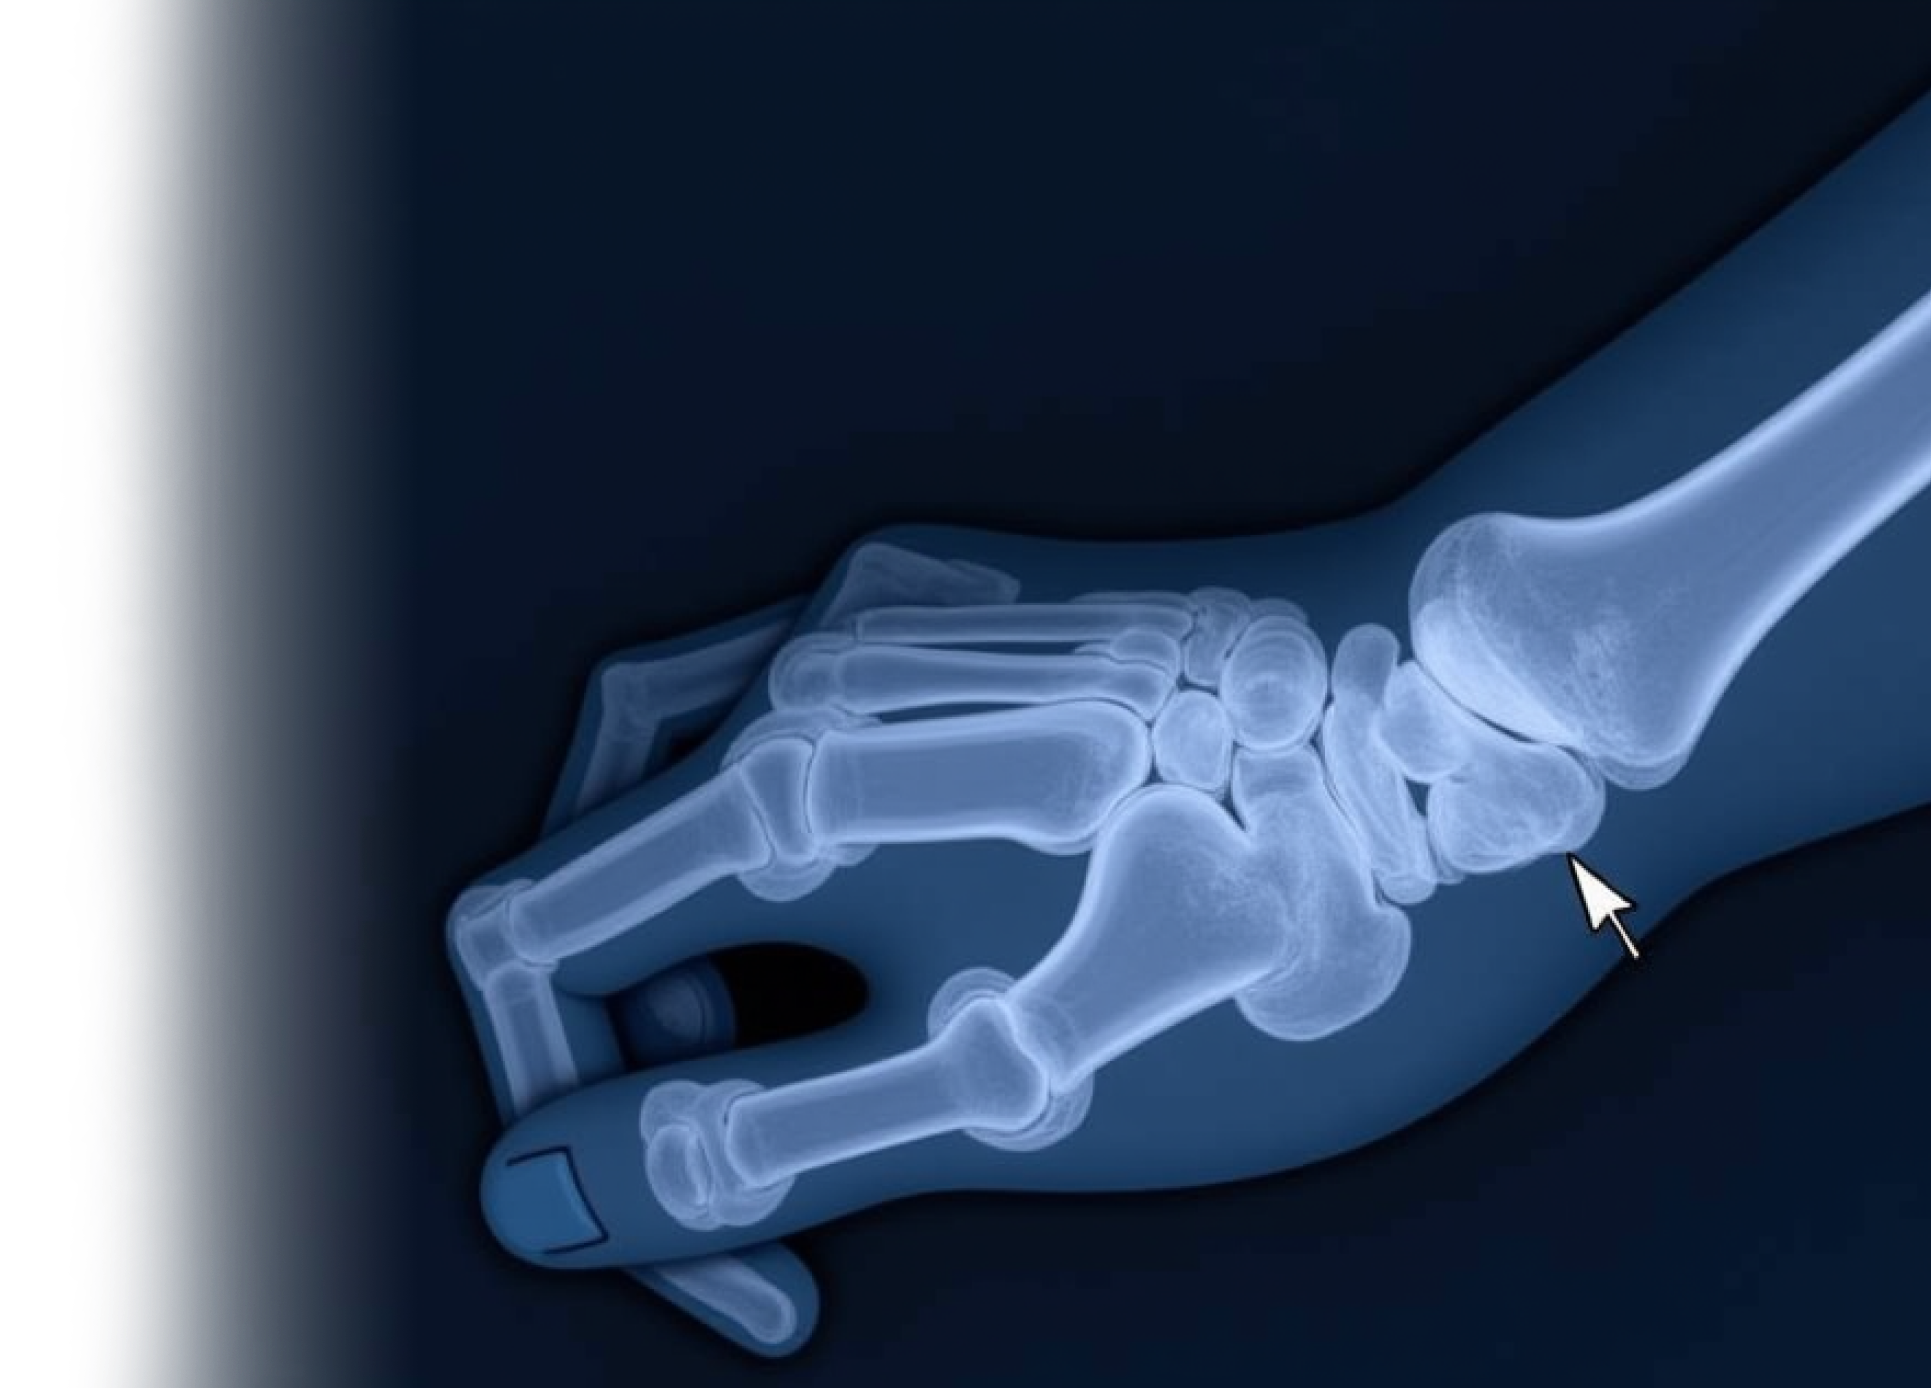

КТ кисти КТ кисти

КТ кисти

Компьютерная томография кисти – важный метод прицельного исследования состояния кисти.

Это неинвазивное обследование, которое позволяет специалистам провести диагностику различных заболеваний и травм кисти.

КТ позволяет исключить патологию кисти костно-травматологического, дегенеративного генеза, изменений, характерных для системного заболевания.